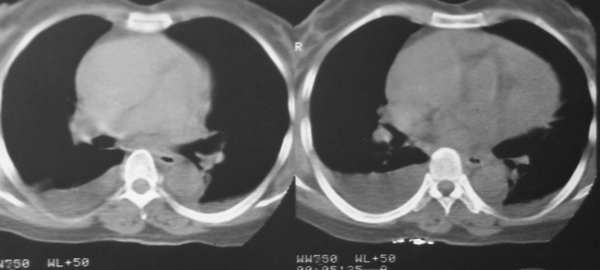

“胸腔积液与心包积液”的诊断可以肯定。结合突然发病的病史,考虑:主动脉窦口破裂可能大。

“胸腔积液”的诊断可以肯定。结合突然发病的病史,考虑:主动脉窦口破裂可能大,引起心包积血。

患者急性起病,影象学表现为大量心包积液和双侧胸腔积液,心包积液密度较高,应该考虑为积血,患者没有外伤史,自发性心包积血应该想到主动脉夹层动脉瘤心包内部分破裂的可能,主动脉根部明显增粗也支持该诊断。关于胸腔积液有两种可能的解释,一是由于夹层的压力很高,造成血性胸腔渗出;另外就是由于心包填塞造成腔静脉系统压力增高,引起胸腔的渗出改变。

不知道患者有无高血压病史,高血压是造成主动脉夹层的最主要原因。

心包大量积液,双侧行腔积液,升主动脉增宽,结合突然发病,不排除主动脉夹层破裂。

回11楼,患者有高血压史.谢谢!